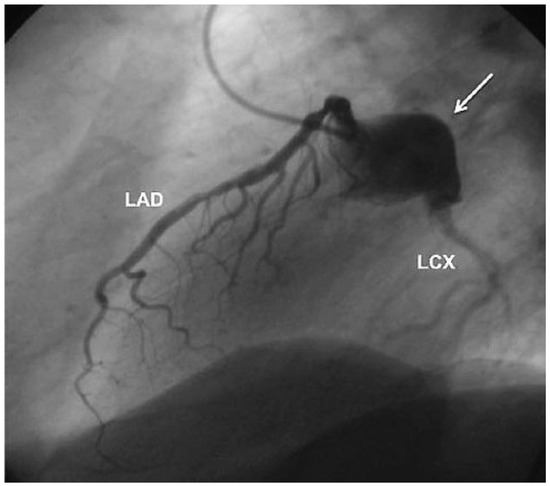

Aneurysm of the Left Circumflex Coronary Artery

by Christian Arranto, Christoph Auf der Maur and Paul Erne

Cardiovasc. Med. 2010, 13(7), 247; https://doi.org/10.4414/cvm.2010.01511 - 11 Aug 2010

Viewed by 66

Abstract

A 54-year-old man was hospitalised because of an inferior ST-elevation myocardial infarction [..] Full article

Show Figures

Figure 1